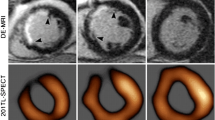

LGE has been found in up to 50% of AFD patients [26]; usually at the LV inferolateral wall with subendocardial involvement, which represents the typical hallmark on CMR (Fig. 4) [26], this typical LGE distribution is useful for differentiating diagnosis in the spectrum of LV symmetrical hypertrophy [27]. LGE has been explained as myocardial fibrosis due to the focal imbalance between the increase in collagen synthesis and decrease in metalloproteinases, caused by glycosphingolipids [28]. LGE together with the maximal wall thickness and cardiac mass represented the best predictor of cardiac events [29], even if in women LGE frequently occurs before LV hypertrophy development [30].

Anderson–Fabry disease—Cine-SSFP in short axis (a) and four-chamber (b) views acquired on end-diastolic phase demonstrate an asymmetrical hypertrophy with predominant involvement of septum (IVS maximal thickness: 20 mm). On LGE image (c), an area of mid-myocardial enhancement is detected in the LV inferolateral wall (red arrow). STIR T2-weighted image (d) shows an area of myocardial edema located in LV antero-lateral wall, with a subendocardial distribution pattern (white arrow), confirmed by the blue area (T2 ratio > 2) in the panel at the bottom. The analysis of nT1 (e) map demonstrates severe reduction in global nT1 (reddish brown color, nT1: 877 ± 23 ms, normal value for our scanner 970–1020 ms) except for the focus of increased nT1 at inferolateral wall (nT1: 1116 ms, black arrowhead) matching the area of increase in ECV (white arrowhead, ECV: 48%) on relative map (f, global ECV: 27%). Hematoxylin and eosin histology (g, ×200) shows cardiomyocytes hypertrophy, caused by large cytoplasmic and perinuclear vacuoles, containing myelin bodies. Cine-SSFP steady-state free precession images; IVS interventricular septum; LGE late gadolinium enhancement; STIR short tau inversion recovery; LV left ventricle; nT1 native T1 map; ECV extracellular volume fraction

As validated in various studies [31–34], myocardial nT1 values are globally decreased, as a consequence of the myocardial accumulation of glycosphingolipids [31], and may discriminate from other infiltrative cardiomyopathies that, apart from iron overload, are usually associated with normal or incremented T1 values [32, 33].

In a study performed on 123 patients, nT1 distinguished AFD from hypertrophic cardiomyopathy (HCM) and healthy controls (sensitivity 88% and 88%, specificity 92% and 86%, respectively) using a cutoff value of 940 ms on a 1.5 T scanner and modified lock–locker inversion (MOLLI) recovery sequence, whereas a better diagnostic performance is obtained with 3.0T scanner (sensitivity 97%, specificity 93%, threshold of 1220 ms) [35]. Myocardial nT1 lowering has also been observed in 41–59% of AFD patients with no LV hypertrophy [32, 36], thus appearing an early marker of disease progression and predictor of clinical worsening at a 12-month follow-up [36]. Myocardial ECV is generally preserved in AFD patients (with lower values in males compared to females [33]).

CMR has emerged as the best noninvasive method to quantitatively assess the myocardial iron load [40, 42]. In non-iron overloaded hearts, the signal is homogeneous and relaxation time lasts for a longer duration. In IOC, the paramagnetic effect of iron produces changes in MR signal intensity and shortens T1 and T2 relaxation times (Fig. 5).

Cardiac iron overload—A 42-year-old woman with Cooley’s disease and moderate reduction in ventricular function (EF: 42%) show a global myocardial hypointensity on STIR image (a) and a diffuse inhomogeneous abnormal signal on LGE imaging (b), with no evidence of clear focal areas of enhancement. Analysis of T2* map (c), generated by traditional multiecho gradient echo T2-weighted sequence, shows a diffuse and marked reduction in the global myocardial T2* relaxation time (T2* = 0–1.5 ms, normal value > 20 ms). nT1 map (d) shows a significant reduction in global nT1 value (nT1 ≈ 535 ms, normal value 970–1020 ms), affected by susceptibility effect of intramyocardial iron accumulation. ECV map e reveals diffuse fibrosis (ECV ≈ 38–40%). STIR short tau inversion recovery; LGE late gadolinium enhancement; nT1 native T1 value; ECV extracellular volume fraction

In particular, iron deposits create a rapid signal loss with increasing echo time that can be better assessed as a reduction in T2* time, calculated with an exponential function using a multiecho gradient echo sequence [43]. T2* measured in a full-thickness region of interest within the interventricular septum is considered highly representative of global myocardial iron [43].

A value of 20 ms is considered the best performing threshold to define myocardial siderosis at 1.5T scanner [41]. Myocardial T2* values > 20 ms measured on 1.5T scanner (12 ms on 3.0T scanner), corresponding to lack of iron overload or benign iron load, are associated with normal cardiac function with a high negative predictive value.

T2* value ranging from 10 ms to 20 ms at 1.5T (from 5.5 ms to 12 ms at 3.0T) is highly indicative of moderate myocardial siderosis and it is correlated with LV ejection fraction [44], and T2* values < 10 ms (< 5.5 ms at 3.0 T) are indicative of severe iron overload, associated with an increased risk of the development of heart failure or arrhythmias [41, 44].

T2* relaxation time is not correlated with serum ferritin levels, although there is a strong correlation with the quantified amount of iron deposition from myocardial biopsy [41]. T2* imaging has also emerged as the best quantitative parameter to guide and assess response to chelation therapy [45] and to monitor disease progression, and is currently the only parametric mapping technique recommended in disease-specific clinical guidelines [46].

Although the T2* technique remains the reference technique for clinical assessment of iron overload, great advantages are offered by the novel T1 and T2 mapping sequences, since myocardial values are reduced in both sequences [46].